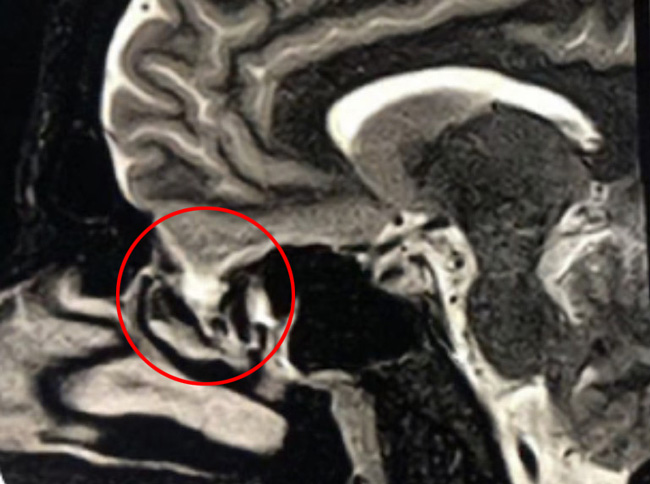

This is a 39 year old physician with a long history of sinus issues, who more recently had noted an increased drainage of clear fluid from his nose. Testing of the fluid for Beta-2-transferrin demonstrated that it was consistent with cerebrospinal fluid (csf). MRI and CT scan demonstrated an encephalocele in the frontal most part of the anterior skull base, on the left, just off midline (Figures 1a,1b,1c). For the last 3 weeks, he has also been having headaches and neck pain.

Figure 1c – Sagittal T2 MRI

Encephaloceles are defects in which the brain exits the skull through defects in the skull. They are usually discovered at birth, and usually present as obvious protrusions from the head. However, it is possible to have an encephalocele present during adulthood, as in this case. The skull defect through which the brain protruded was from the anterior skull base into the ethmoid sinus, so it would not have been grossly noticeable. It is unclear whether some of this patient’s chronic sinus issues may have been secondary to this encephalocele, or may have ultimately led it to tear, and start leaking csf from the nose. Regardless, in light of the csf rhinorrhea, surgery was indicated to repair the defect to stop the csf leak and prevent the development of meningitis or brain abscess.